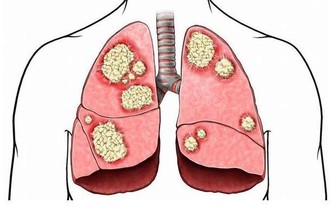

若還有憋氣、明顯的紫紺、口唇發紫、血氧下降等,就要高度懷疑可能是肺栓塞。

6.潛在病因:除了疼痛,還要警惕可能導致猝死的潛在病因。

比如,是否有易形成血栓的病史。

例如一位骨折病人,他 曾在一段時期內被限制運動,那麼他就容易發生靜脈血栓,

而靜脈血栓一旦掉下來,則可能發生肺梗死。